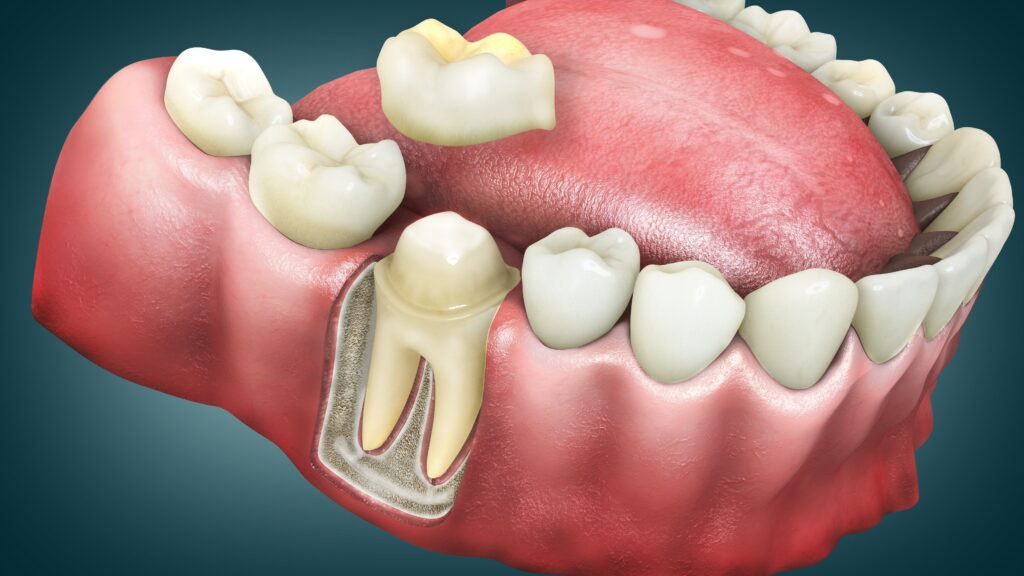

Sharp jolts when you sip coffee? Throbbing ache that keeps you up at night? If you’re dealing with tooth pain that won’t quit, root canals

Sharp jolts when you sip coffee? Throbbing ache that keeps you up at night? If you’re dealing with tooth pain that won’t quit, root canals